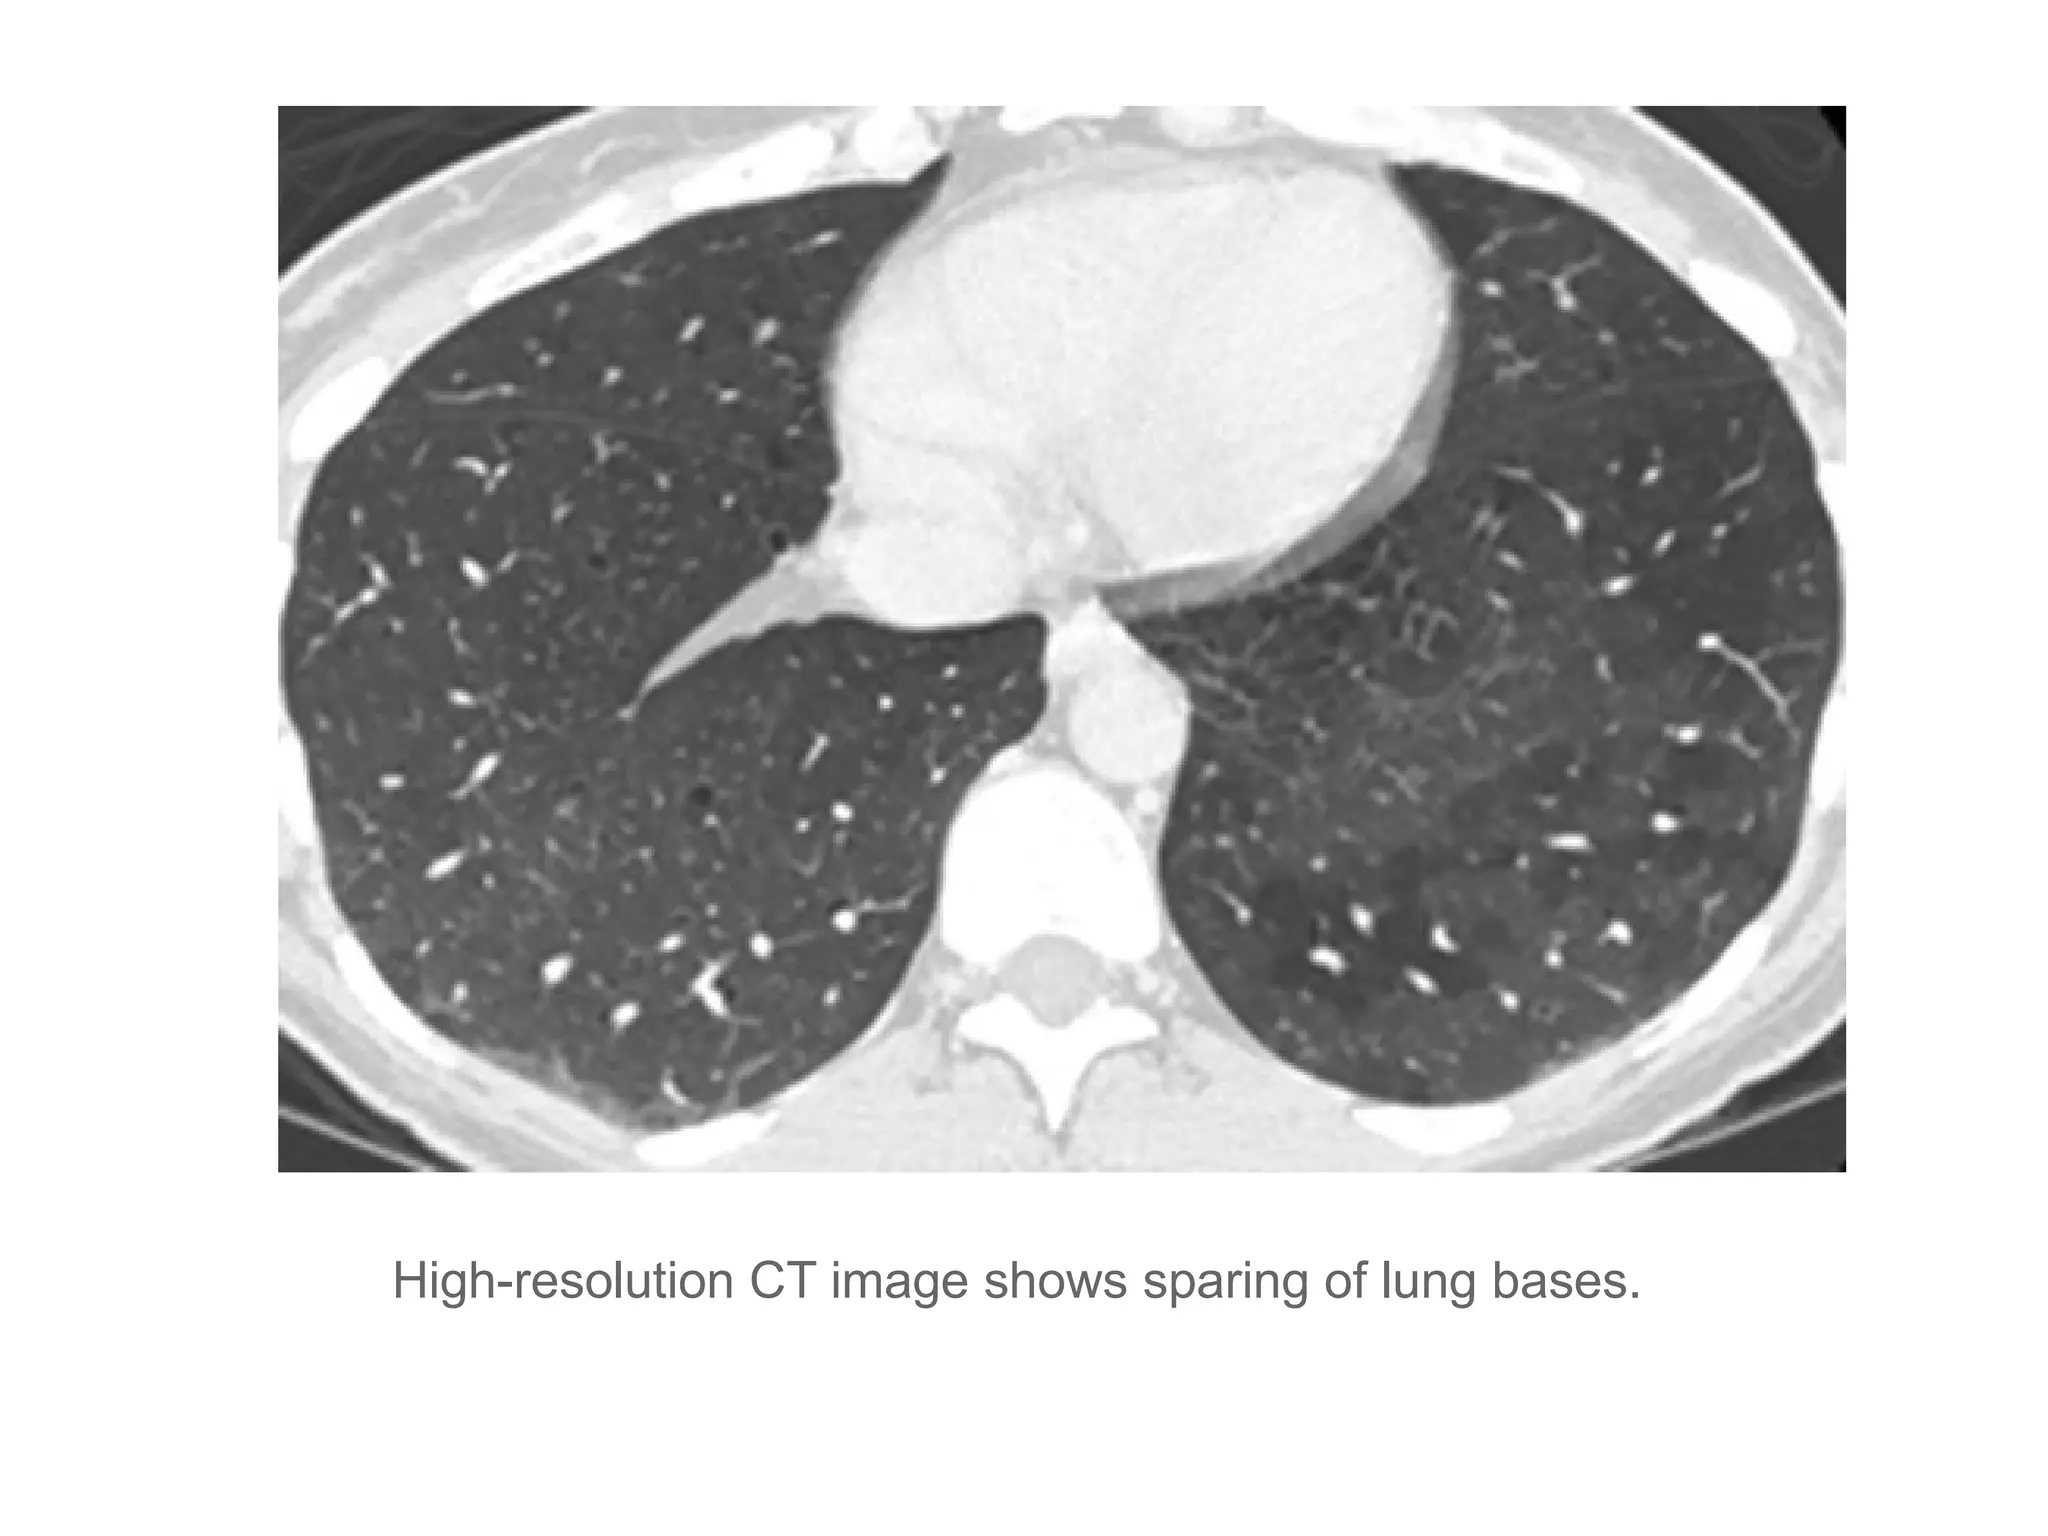

High-resolution CT image shows sparing of lung bases.

Langerhans cell histiocytosis •Smokers, Females = Males • Nodules and cysts • Cysts have wall of variable thickness • “bizarre shaped cysts” • Mid to upper lung predominance • Spares CP angles • Ill defined nodules → Ill defined nodules + bizarre shaped cysts → Bizarre shaped cysts • May be associated with other smoking related diseases – RB-ILD, Emphysema.

High-resolution CT imageshows thin-walled cysts. Cysts may be round but are frequently irregular, bilobed (arrow), cloverleaf-shaped, or bizarre shapes. Note striking upper lobe predominance.

High-resolution CT imageshows sparing of lung bases.